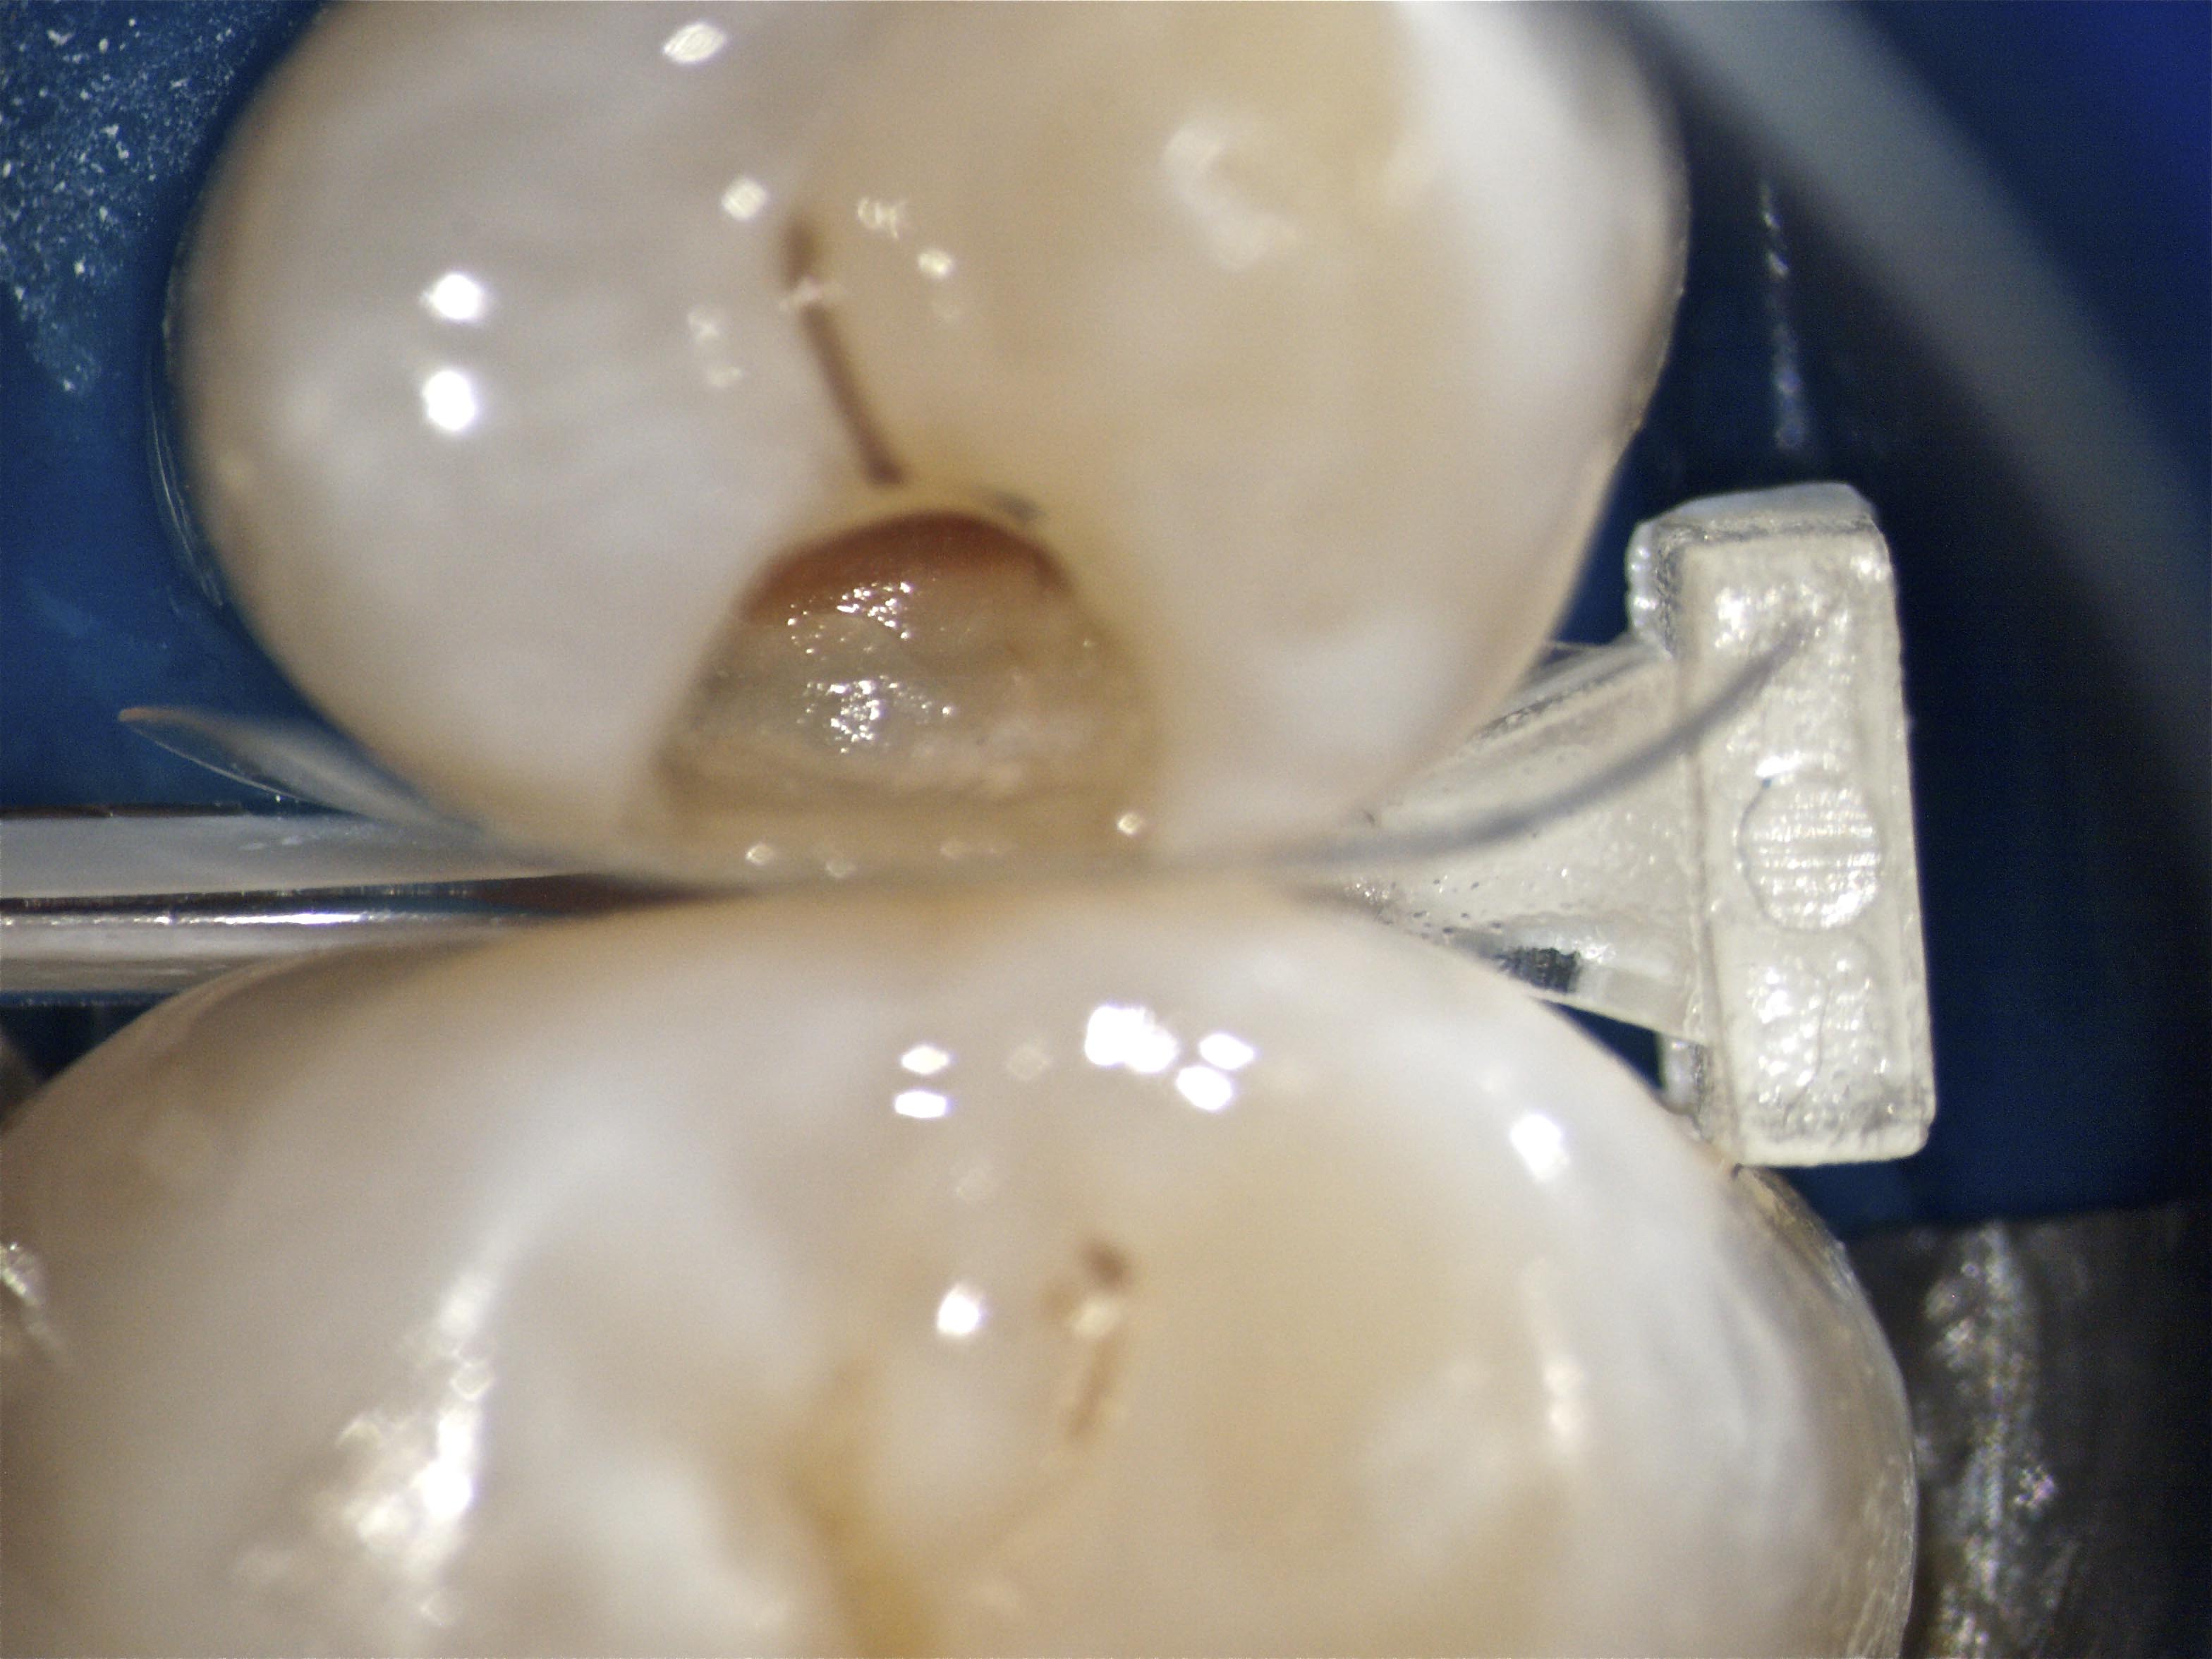

OLYMPUS DIGITAL CAMERA Veröffentlicht 20. März 2011 am 3136 × 2352 in GH1 – Fotos am Dentalmikroskop – Update